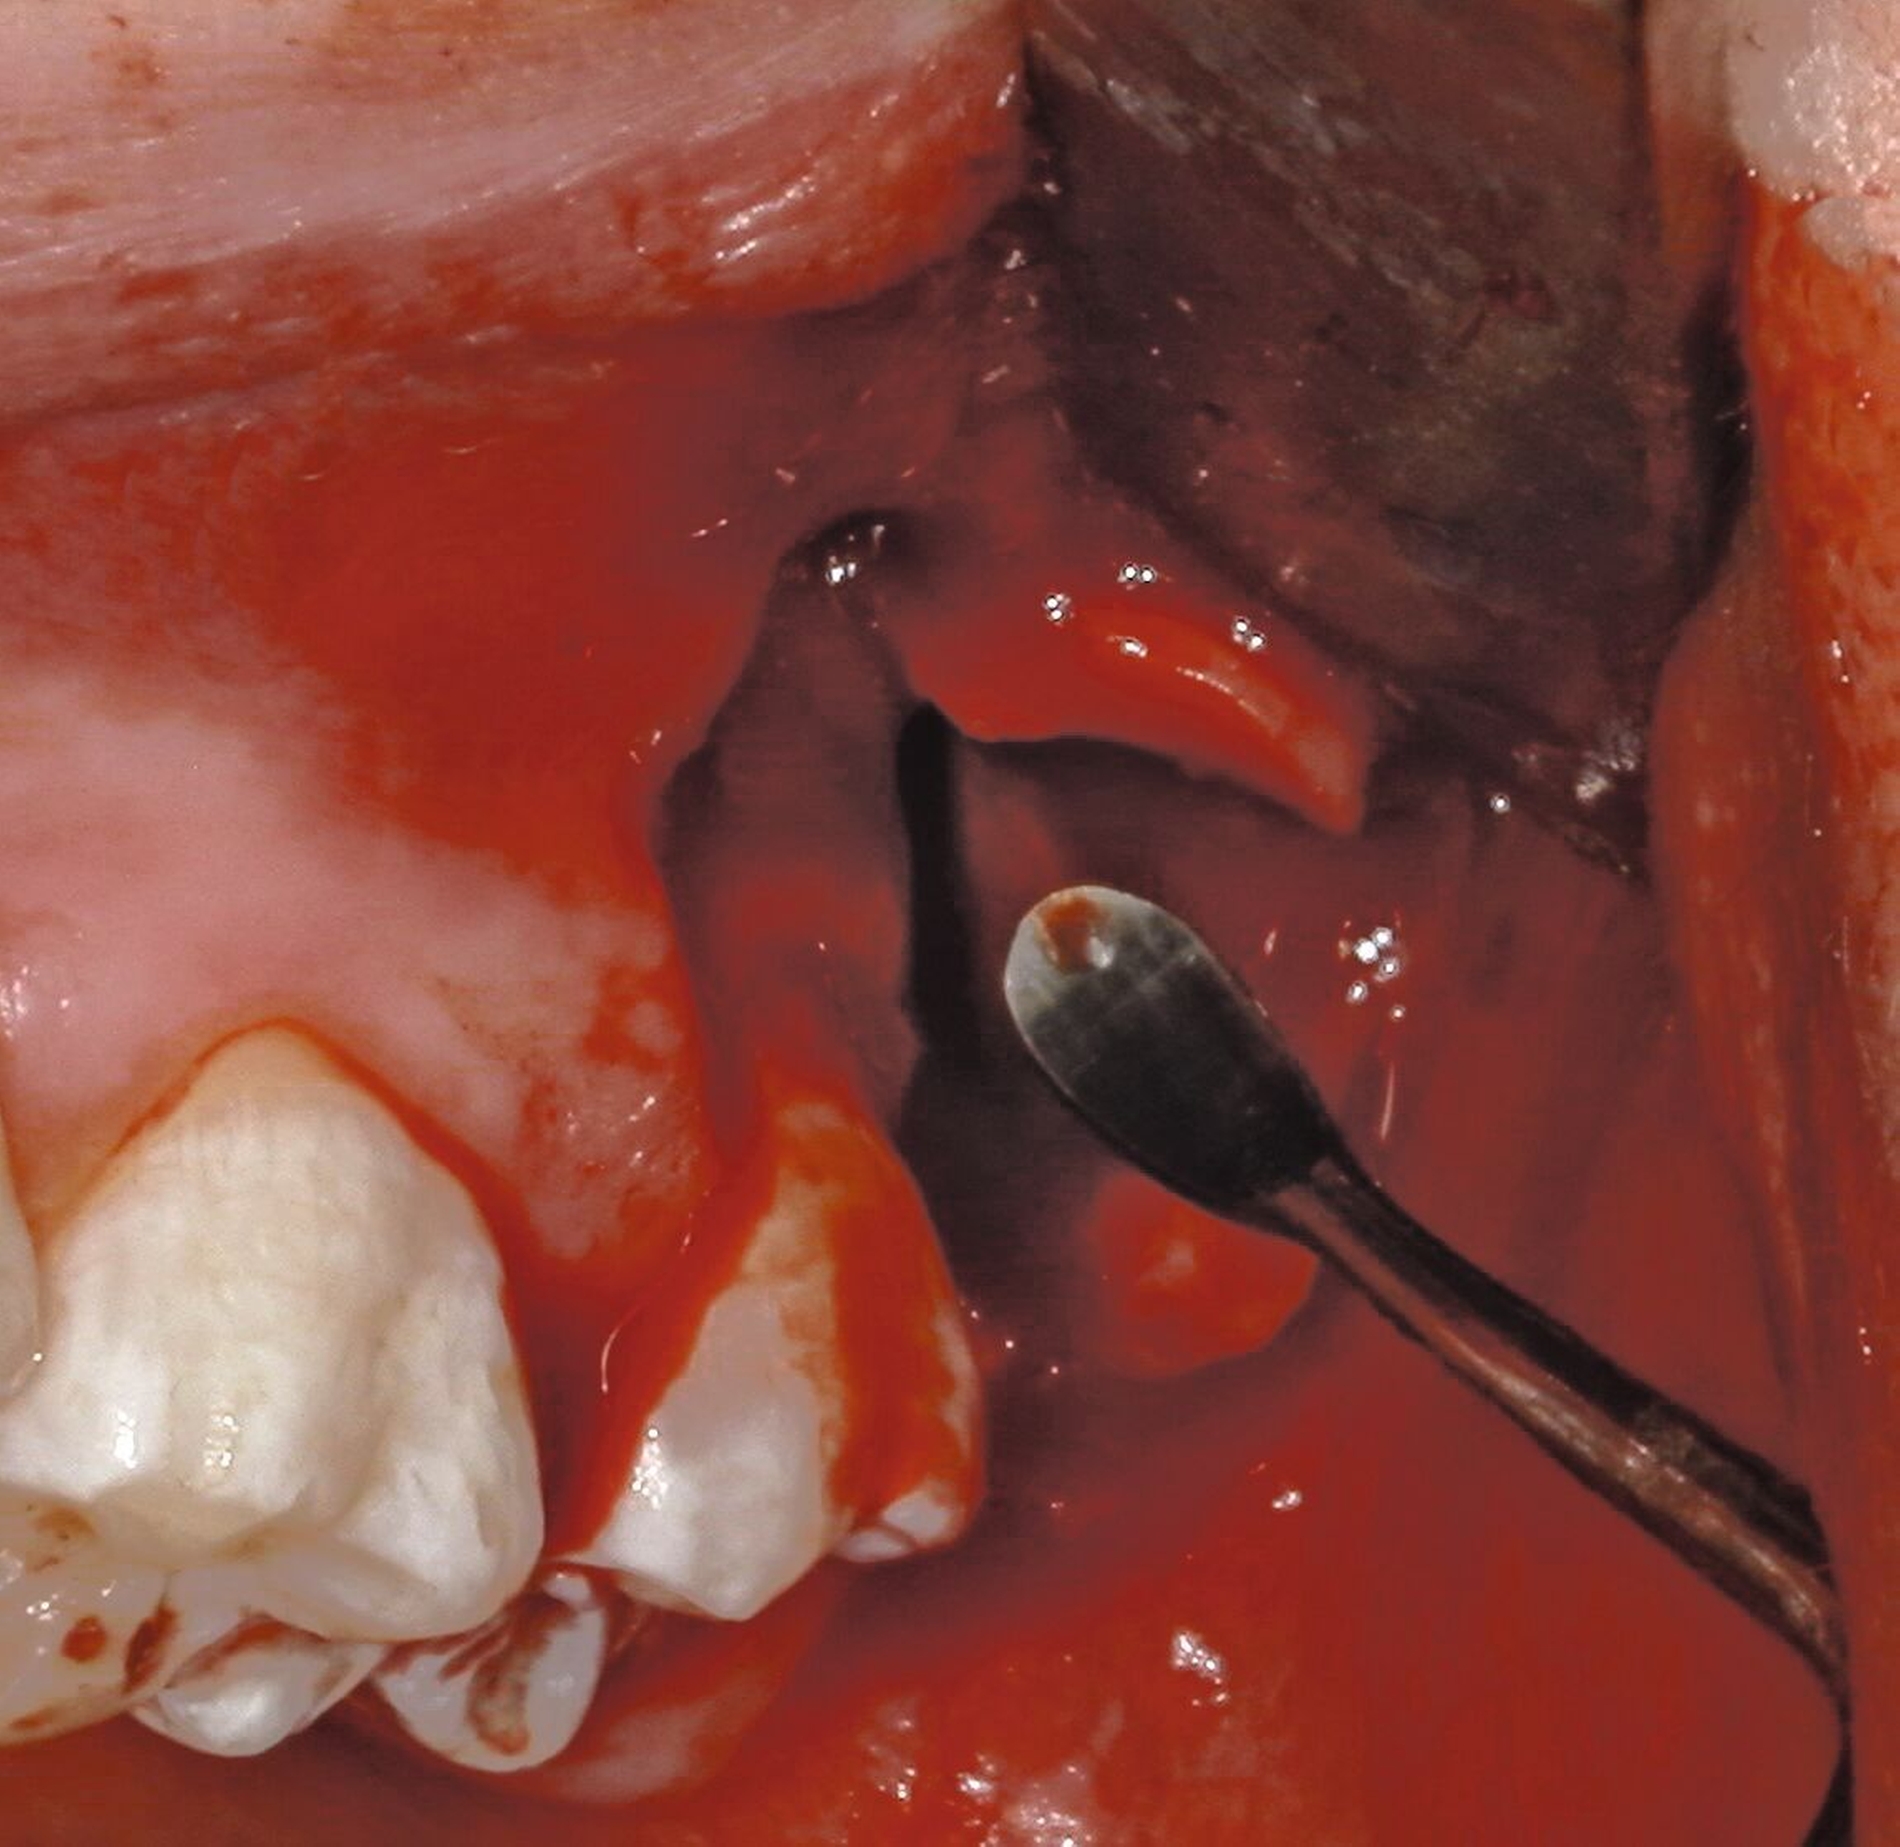

Anschließend erfolgt die sorgfältige Kürettage unter Schutz des am Boden der Extraktionsalveole liegenden Canalis mandibularis, die Entfernung von Granulationsgewebe sowie des Follikelepithels. Die Wurzelspitze sollte auf Vollständigkeit überprüft werden, um eine Wurzelfraktur auszuschließen (Abbildung 11).